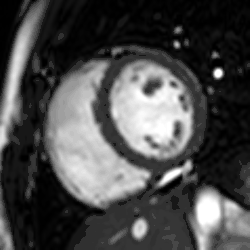

Perfusion

Adenosine is used as a vasodilator, via the A2A receptor, to increase the difference in perfusion between myocardial territories supplied by normal and stenosed coronary arteries. A continuous intravenous infusion is administered for a few minutes until there are hemodynamic signs of vasodilatation, then a bolus of contrast medium is administered while acquiring saturation recovery images of the heart with a high temporal resolution readout. A positive result is evident from an inducible myocardial perfusion defect. Cost and availability mean that its use is often confined to patients with intermediate pre-test probability,[24] but it has been shown to reduce unnecessary angiography compared with guidelines-directed care.[25]

CMR perfusion. Inducible perfusion defect in the inferior wall.